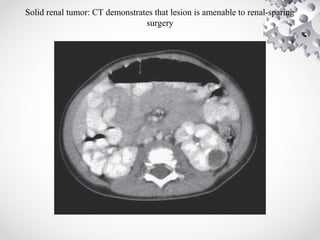

Solid renal tumor: CT demonstrates that lesion is amenable to renal-sparing

surgery

• CT SCAN:

helps to determine origin of the tumor, lymph

node involvement, B/L kidney involvement,

invasion into major vessels (IVC), and liver

metastases.

CT chest to rule out lung metastasis.

Solid renal tumor:CT demonstrates that lesion is amenable to renal-sparing surgery

• CT SCAN: helpsto determine origin of the tumor, lymph node involvement, B/L kidney involvement, invasion into major vessels (IVC), and liver metastases. CT chest to rule out lung metastasis.